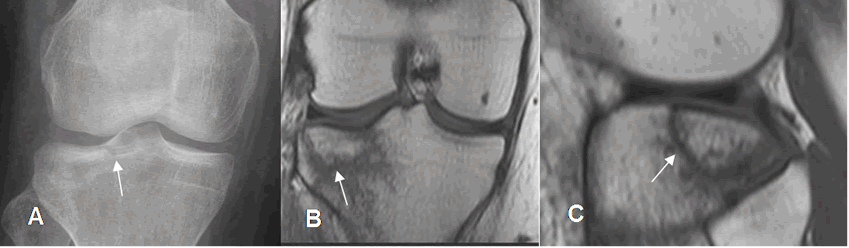

Fig 42. Fractura de la tibia.

A: Rx AP. Imágenes radiolúcidas en el tercio proximal de la tibia, por fracturas no desplazadas.

B: RM coronal en T1 y C: RM coronal en STIR. Imágenes hipointensas en T1 e hiperintensas en STIR, por fracturas no desplazadas.